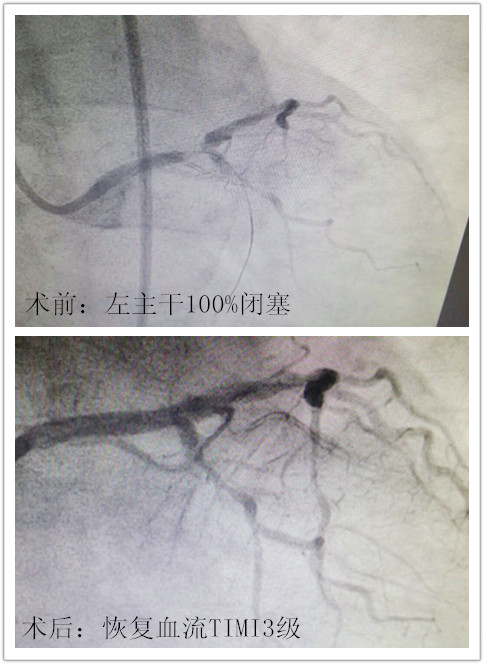

当时患者情况从造影结果来看十分不乐观,左主干远端已经完全闭塞,就像是本应蜿蜒向前的路因雪崩成了悬崖,随时有猝死的危险。尚怡君主任向患者家属交代病情,得到家属同意后立即上台为患者行支架介入治疗。

尚怡君主任带领李恒斌副主任医师、荀平主治医师立即开始紧张有序的介入治疗,治疗技术娴熟过硬,采用右侧股动脉穿刺,7F指引导管、CTO导丝、Fancross微导管,球囊扩张、支架置入。在一系列高度精准操作后,患者无任何并发症!近30分钟的左主干介入治疗宣告成功,威胁患者的致命问题得到妥善解决。患者被送回病房,患者家属的欣喜之情溢于脸上。